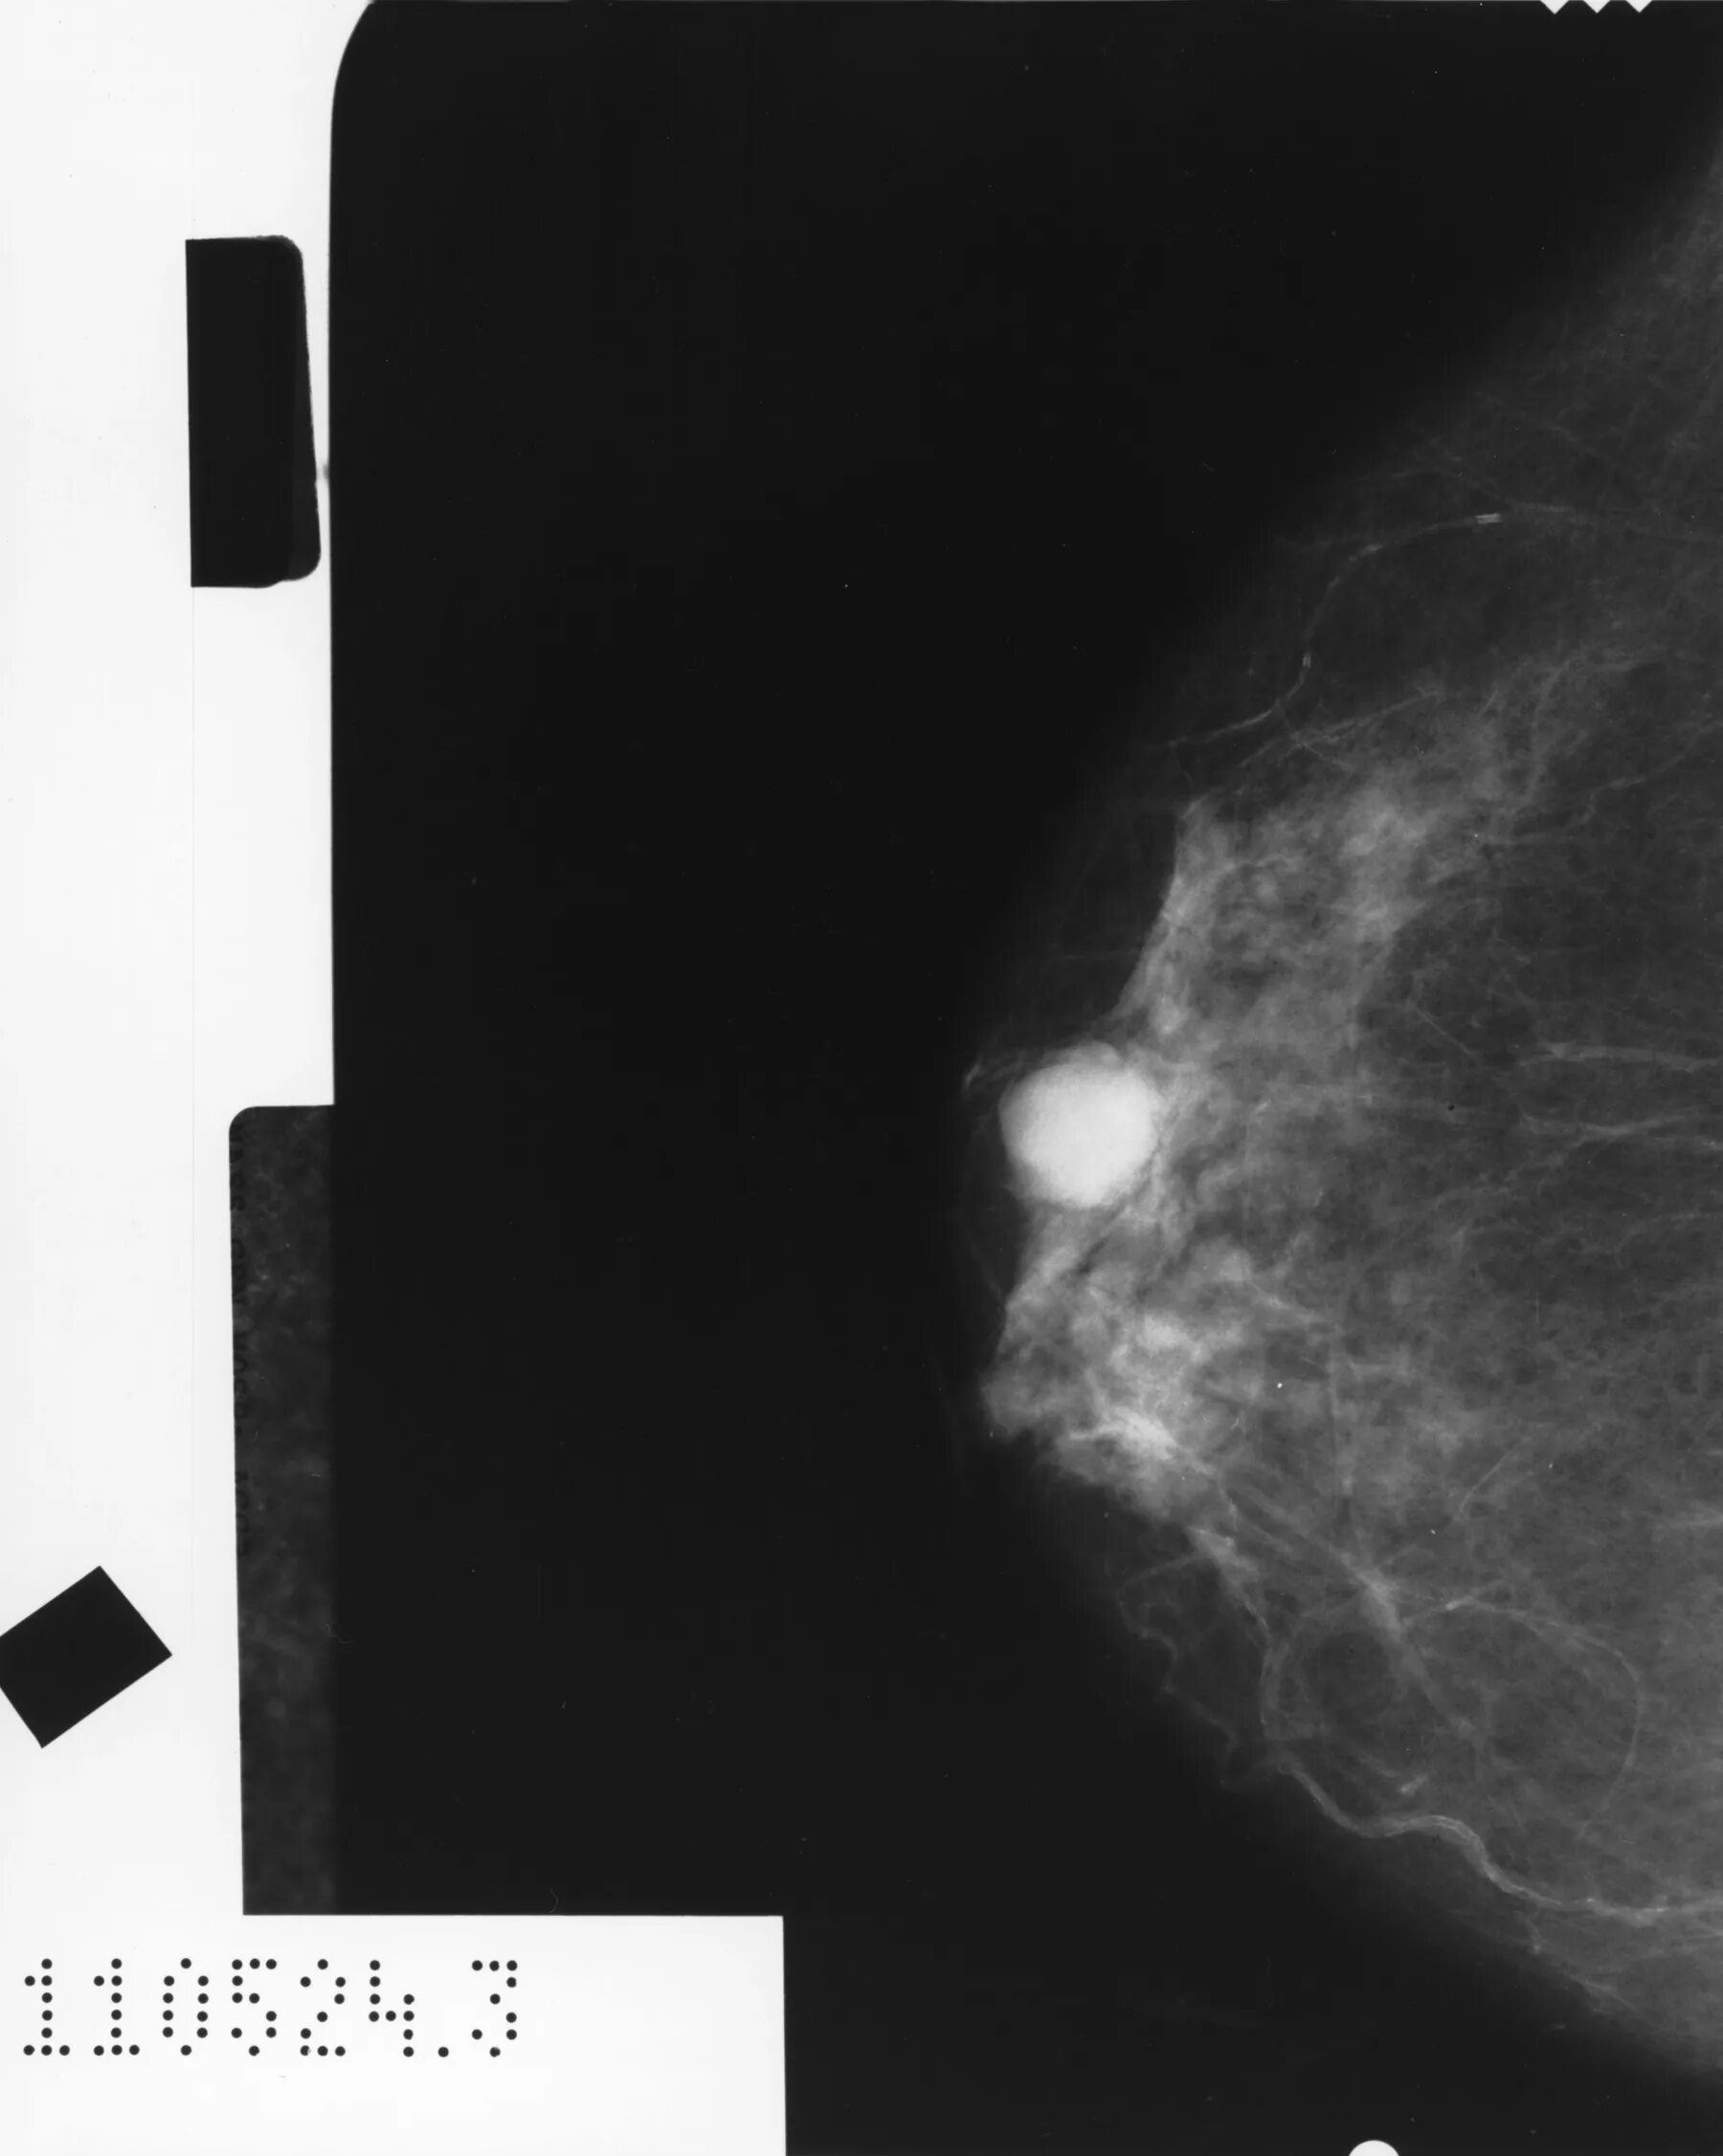

Склерозирующий аденоз молочных желез